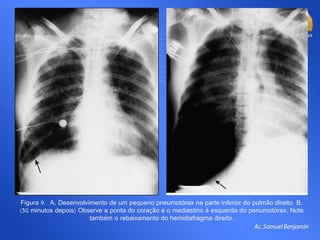

Figura 9. A, Desenvolvimento de um pequeno pneumotórax na parte inferior do pulmão direito. B,

(30 minutos depois) Observe a ponta do coração e o mediastino à esquerda do penumotórax. Note

também o rebaixamento do hemidiafragma direito.

Figura 9. A,Desenvolvimento de um pequeno pneumotórax na parte inferior do pulmão direito. B, (30 minutos depois) Observe a ponta do coração e o mediastino à esquerda do penumotórax. Note também o rebaixamento do hemidiafragma direito.